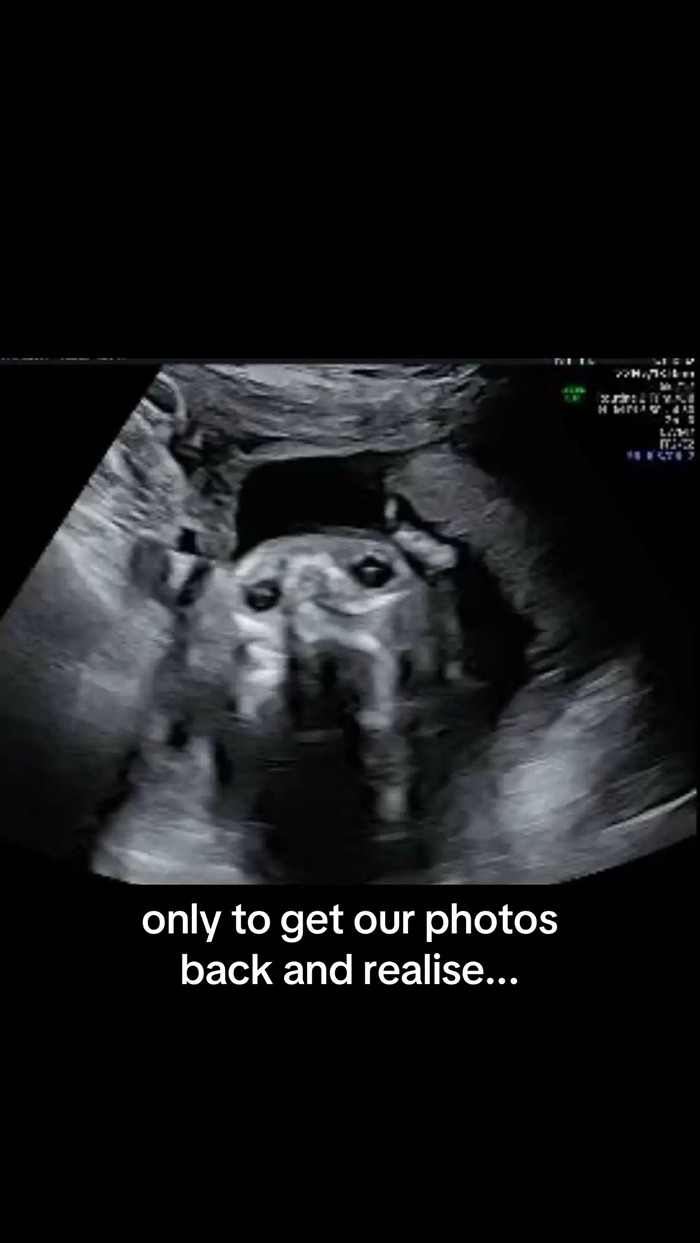

“We were so excited for our anatomy scan,” Egner wrote across the first slide of her post. “Only to get our photos back and realise our son looks remarkably like our dog!”

Egner then sent the image to the rest of her family, who all saw the same thing.

“My father, unprompted, actually said the same thing,” she said. “He responded to that particular picture and said, ‘The baby looks like Goulash.’ No one can unsee it now!”

As for what created the strange, dog-like image. Egner explained to her viewers that it was most likely the result of a weird angle.

“They were checking from the angle of his chin, checking up his nostrils and his eyes,” she said.